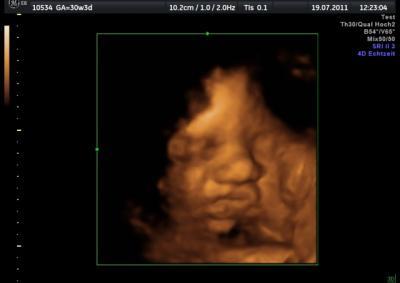

Hier ist ein anderes Bild von unserer kleinen und man sieht das die Nase ok ist. Nicht verrückt machen Mädels...werde gleich selbst noch nervös wegen der Nase. Allen noch ein schön Abend:D

Das vorhin war sicher nur ein Schatten.... Das hatte ich auch schonmal bei einem Bildchen. Alles wird gut. ;o)))) Lg